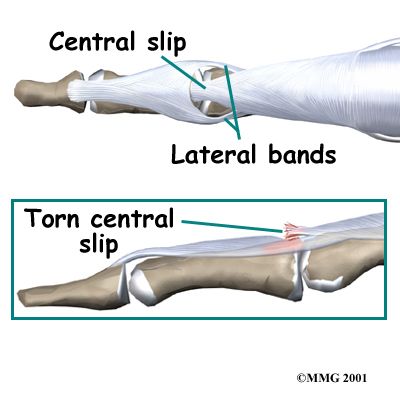

The place where the extensor tendon attaches to the middle phalanx is called the . When the extensor muscles contract, they tug on the extensor tendon and straighten the finger. Problems occur when the central slip is damaged, as can happen with a tear.